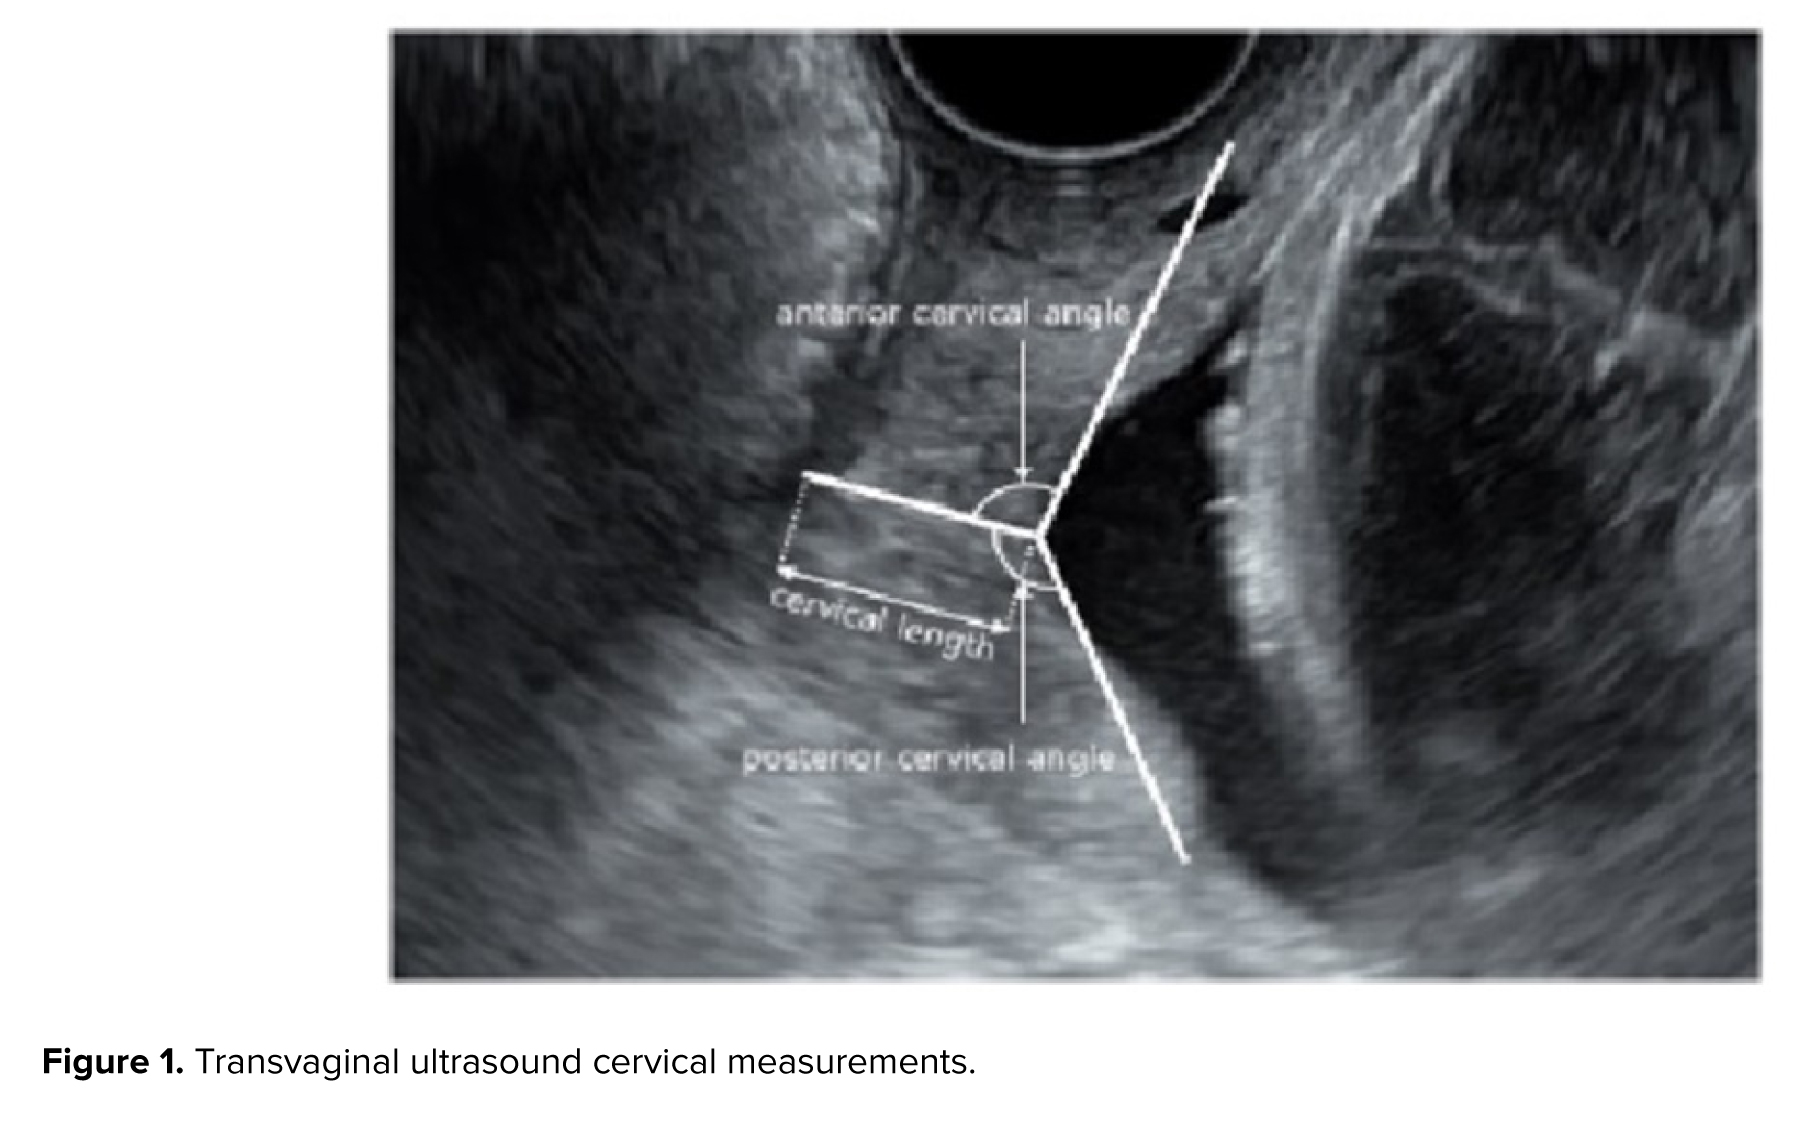

2.4. CAs measurement

Ultrasound examinations were performed by an experienced sonographer using a Philips Affinity 50 ultrasound machine equipped with a 5-9 MHz transvaginal probe. Women were placed in the supine position with hips flexed and abducted, knees flexed, and with an empty bladder. The vaginal transducer was covered with a single-use sterile vinyl sheath. Care was taken to ensure that the ultrasound images included both the internal and external cervical os (the opening of the cervix) as well as the outermost part of the fetal presenting part. The CL was measured as the distance between the internal and external cervical os. The anterior and posterior CA were calculated by drawing 2 lines converging at the internal cervical os. Specifically, the posterior CA was defined as the angle between an imaginary line crossing the cervical canal and another tangential to the posterior uterine wall at its junction with the internal os, assessed in the sagittal plane at the level of the internal os. Presence of funneling was also recorded (Figure 1).